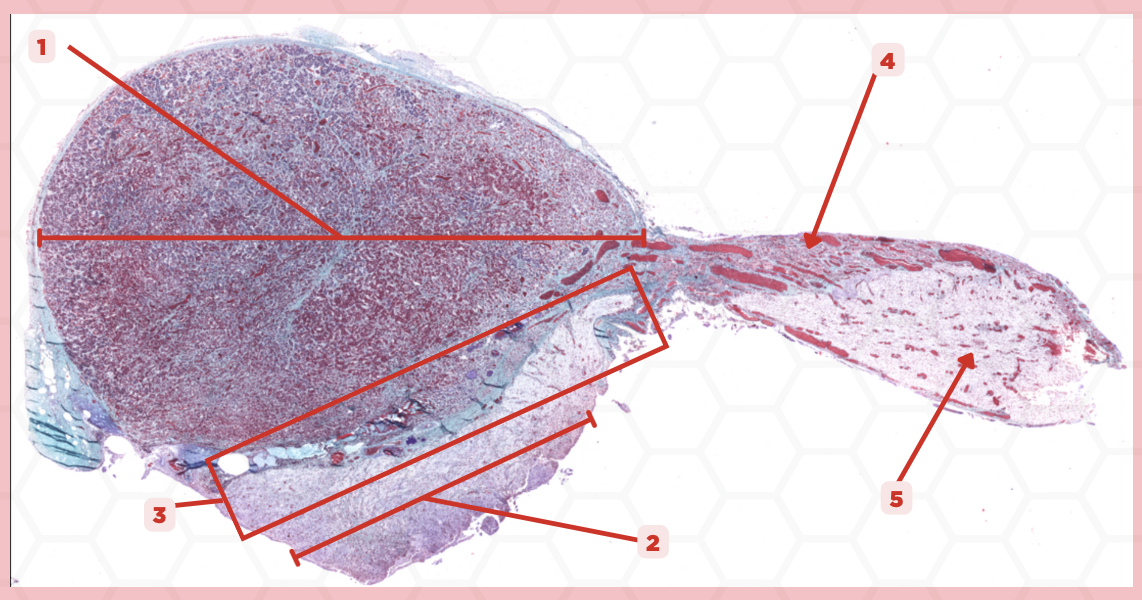

Pituitary

Identify the specimen.

Anterior Lobe

Identify the structure labeled as 1.

Posterior Lobe

Identify the structure labeled as 2.

Intermediate Lobe

Identify the structure labeled as 3.

Pars Tuberalis

Identify the structure labeled as 4.

Pituitary Stalk

Identify the structure labeled as 5.